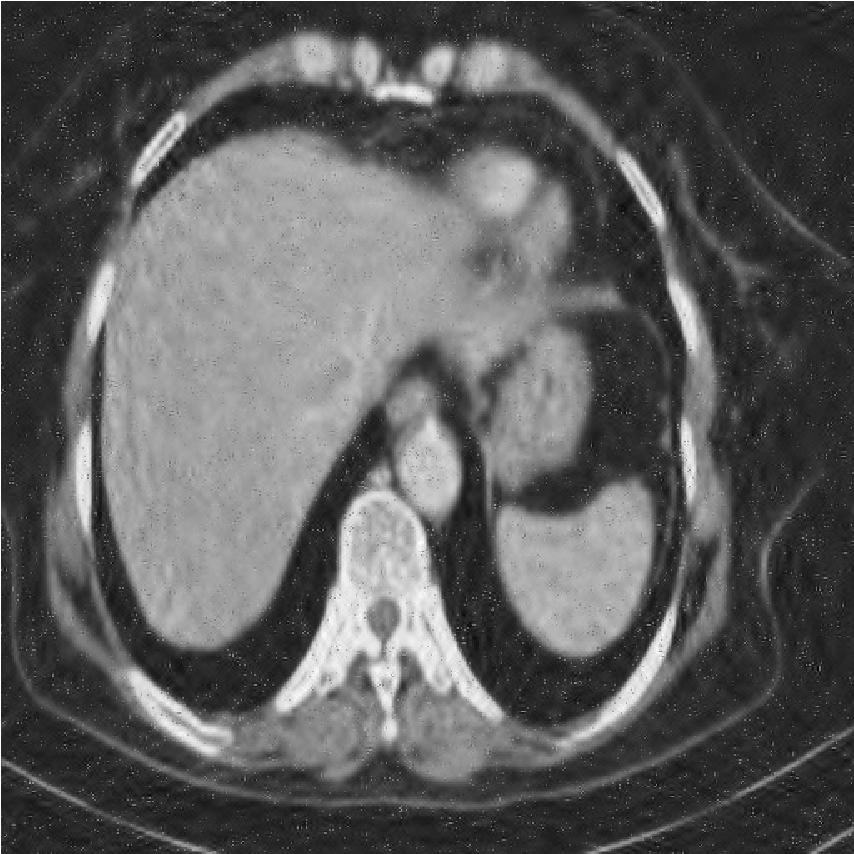

We performed extensive numerical simulations to examine the performance of the aforementioned denoising methods. For this purpose, we used a pixel grayscale CT scan image, shown in Fig. 2a. Noisy versions of this image were created by adding different types of noise at various strengths. The noise types considered are Gaussian noise, uniform noise, salt and pepper noise, and Poisson noise. The following subsections present and explore the results obtained from the various denoising methods. All computational programming were carried out using Mathematica 12.0.

[b)Gaussian]

[c)Uniform]

[d)Poisson]

[e)Salt Pepper]

This finding highlights a critical principle in image processing: the implementation strategy (global vs. local processing) can be as important as the choice of transform itself. Future work could explore local or adaptive wavelet thresholding schemes (e.g., context modeling, spatially varying thresholds) to leverage the strengths of wavelets while incorporating the local adaptability that made DFCT successful in this study. Figs. 8-11 show visual comparison of denoising results for the four kinds of noise. In the Figs. 8-11 the left image is noisy input image, the middle image is denoised image using the best wavelet method (BIOS wavelet with Hyperbola threshold for case of Gaussian and uniform noise, BIOS wavelet for Poisson noise and Daubechies wavelet with SURELevel for salt-and-pepper noise) and, the right image is denoised using DFCT.